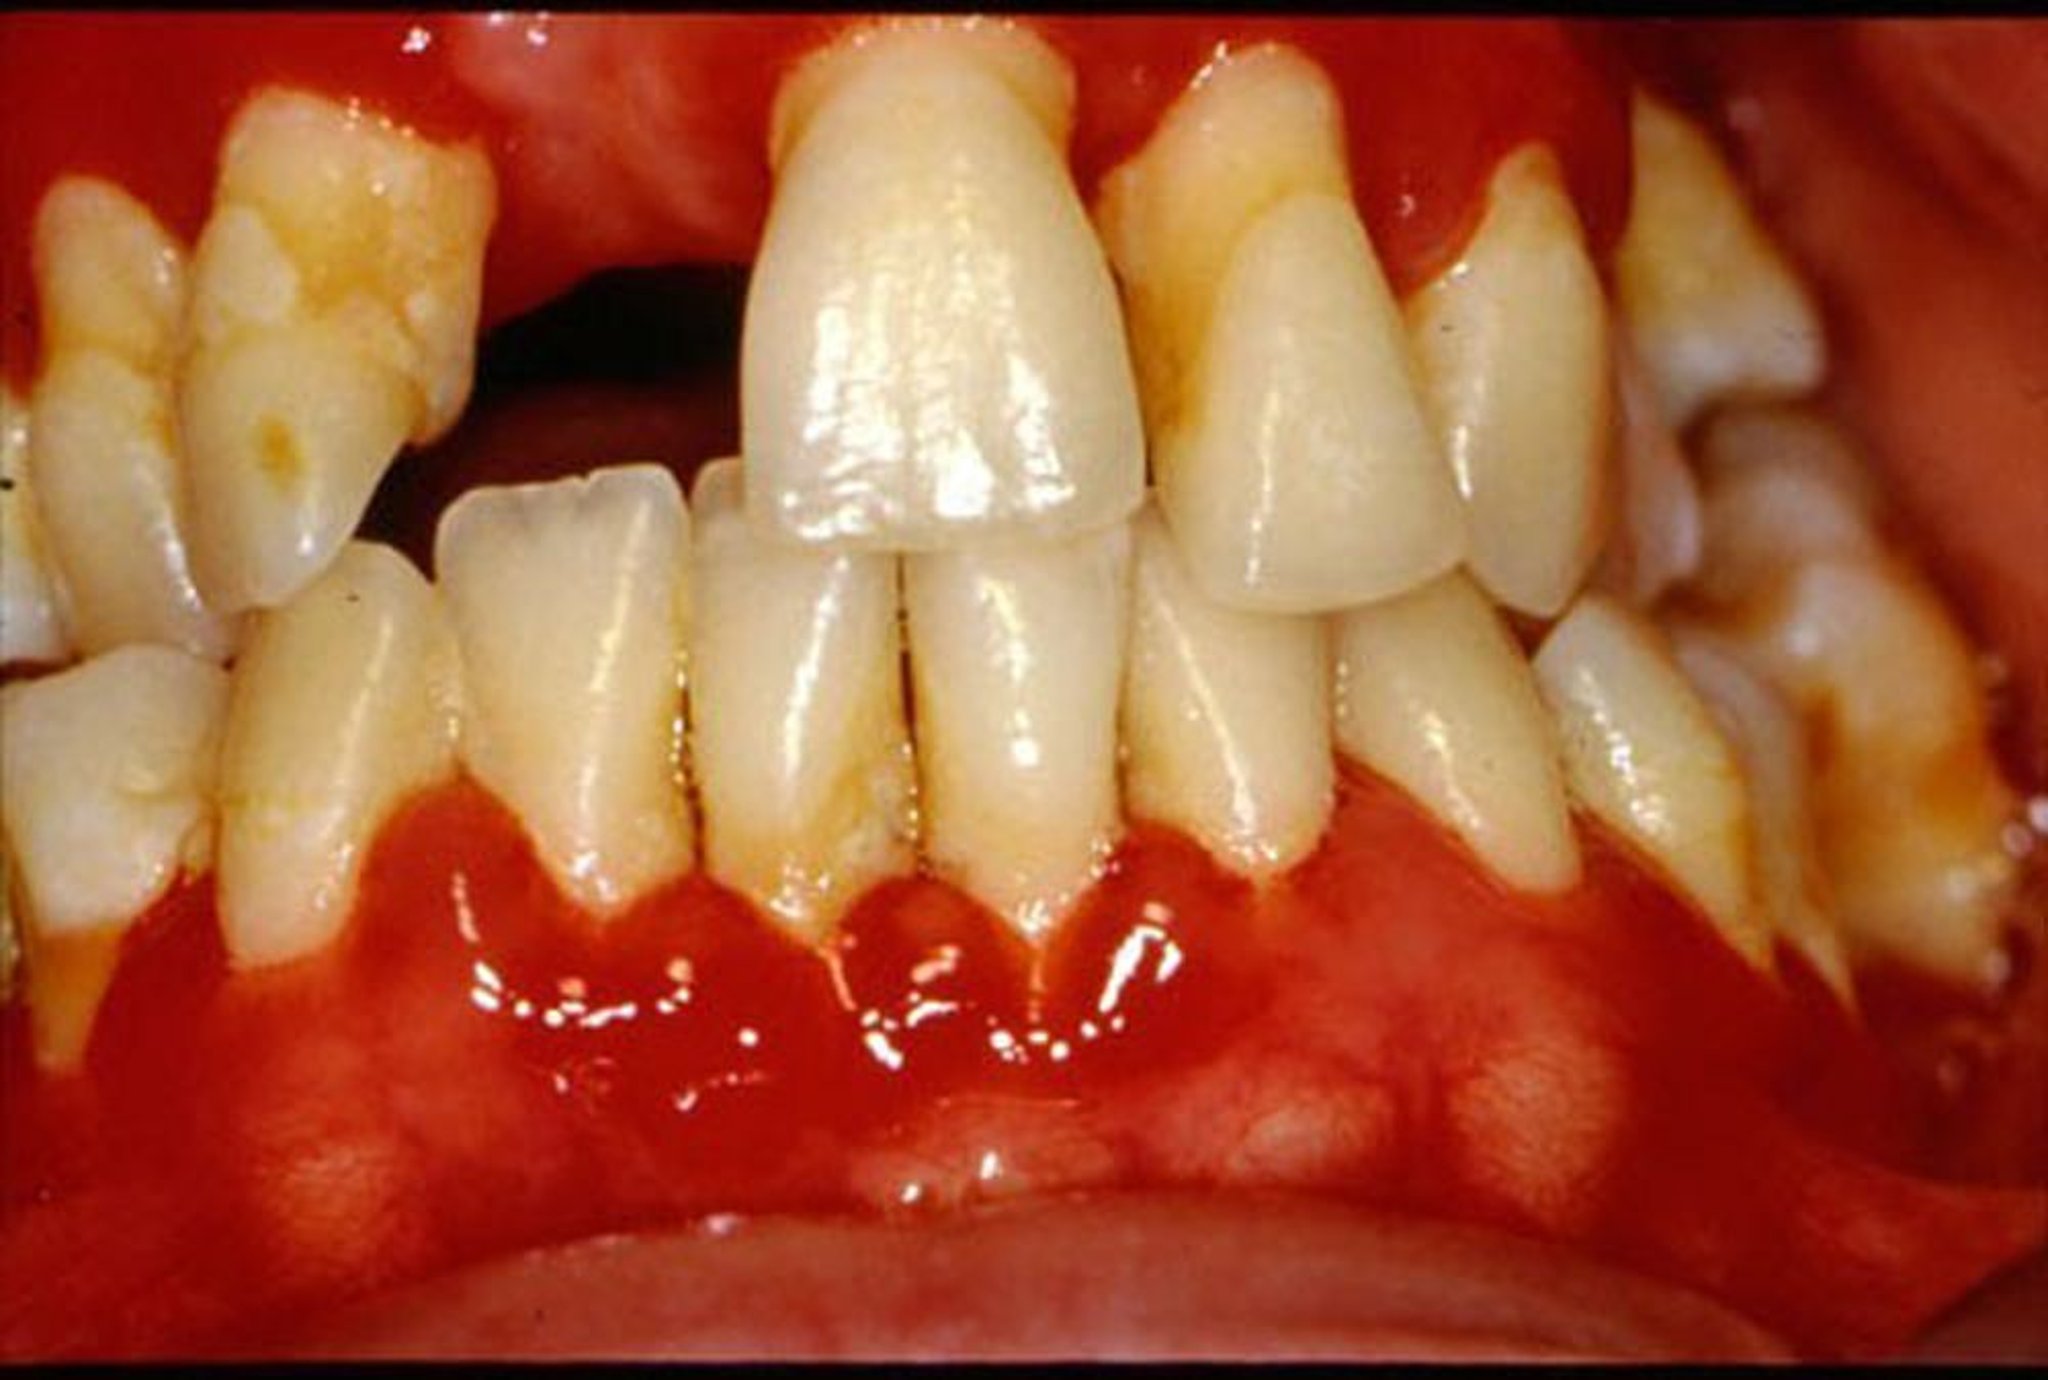

जिंजिवाइटिस के कारण मसूड़े लाल हो जाते हैं और सूज जाते हैं।

जोनाथन ए शिप, DMD द्वारा उपलब्ध कराई गई इमेज।